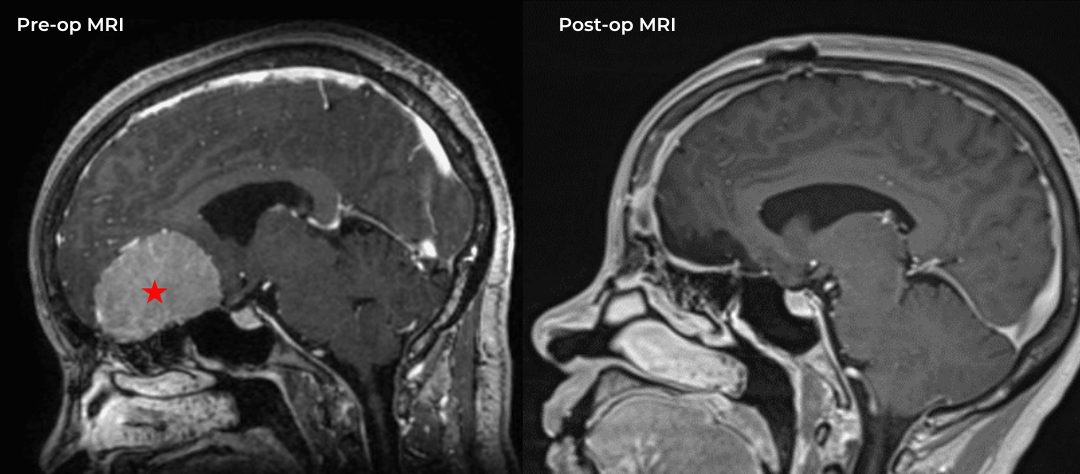

Figure 1a – Preoperative MRI demonstrating an extra-axial enhancing mass of the anterior cranial fossa.

Figure 1b – Postoperative MRI demonstrating a complete resection without residual enhancement.

She was started on high-dose steroid and antiseizure prophylactic medicine. Surgical intervention was offered for mass effect, symptomatic relief, neurologic preservation, and histopathologic diagnosis. Dr. Gaudin performed a bifrontal craniotomy with complete resection of neoplasm through an interhemispheric and subfrontal approach. Postoperative imaging demonstrated a gross total resection without residual tumor and resolution of mass effect (Figure 1b and 2b). Intraoperative pathology was consistent with meningioma, WHO grade 1. She recovered very well, and was discharged home on postoperative day 3. On her follow-up outpatient visit, her preoperative symptoms had fully resolved, and her olfactory sense was maintained.